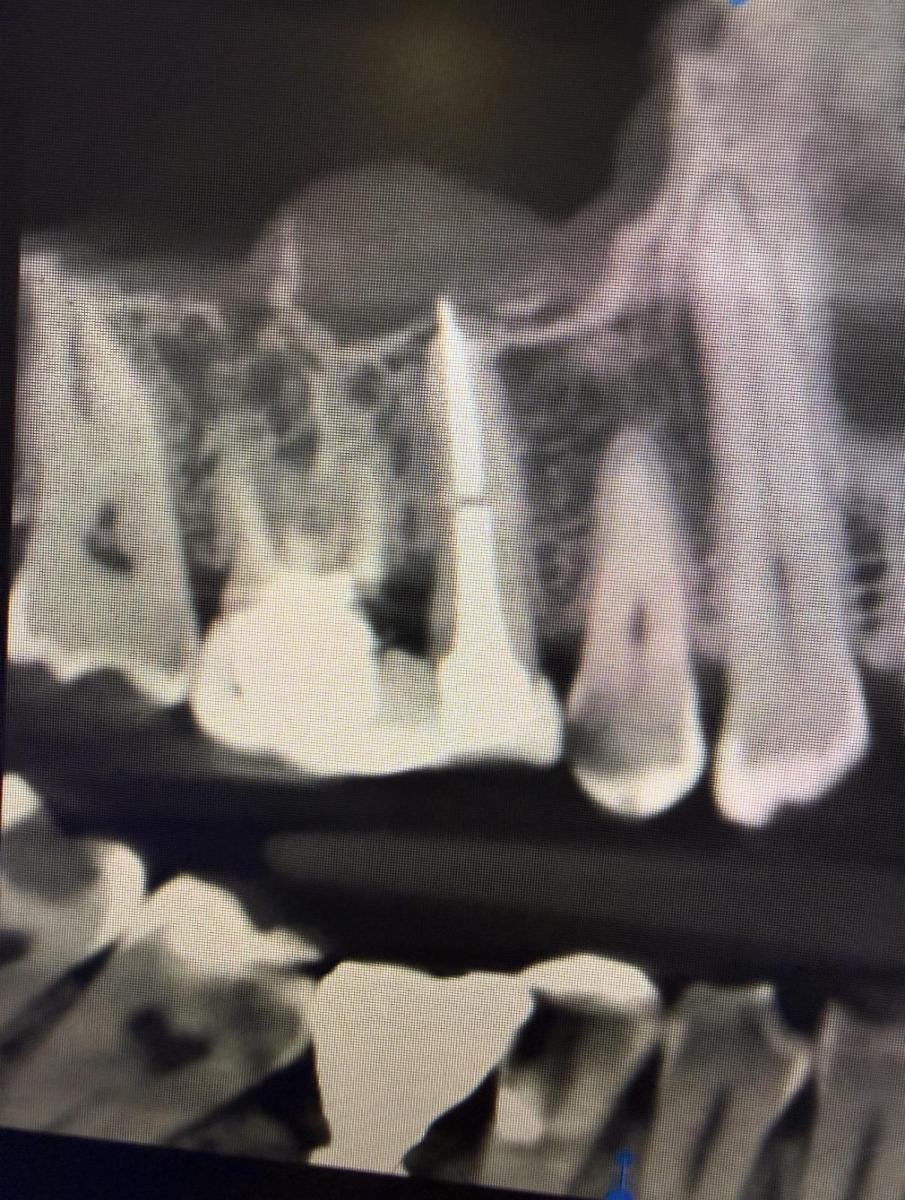

Может ли из-за этого ныть зуб? При лечении делали снимок и все хорошо, а после установки штифта появилось это на снимке видно , что пломба за корень вышла и расстояние в канале между штифтом и пломбой